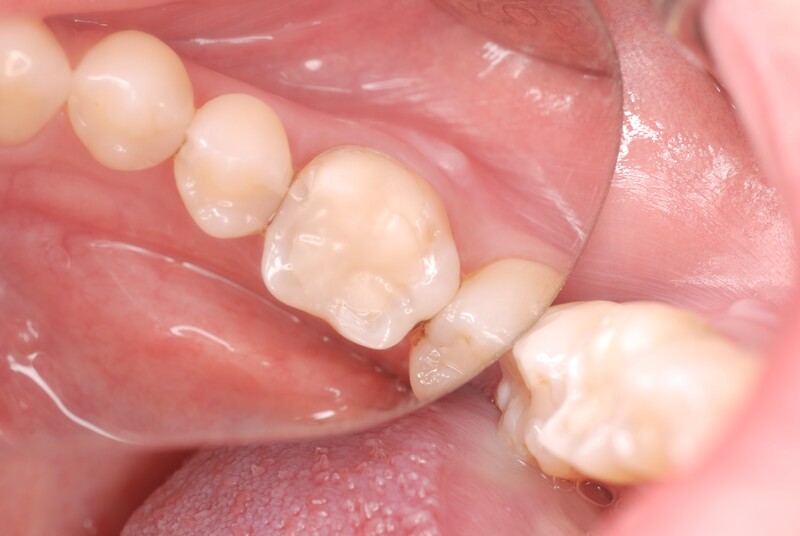

初診時の写真です。歯肉が腫脹しております。